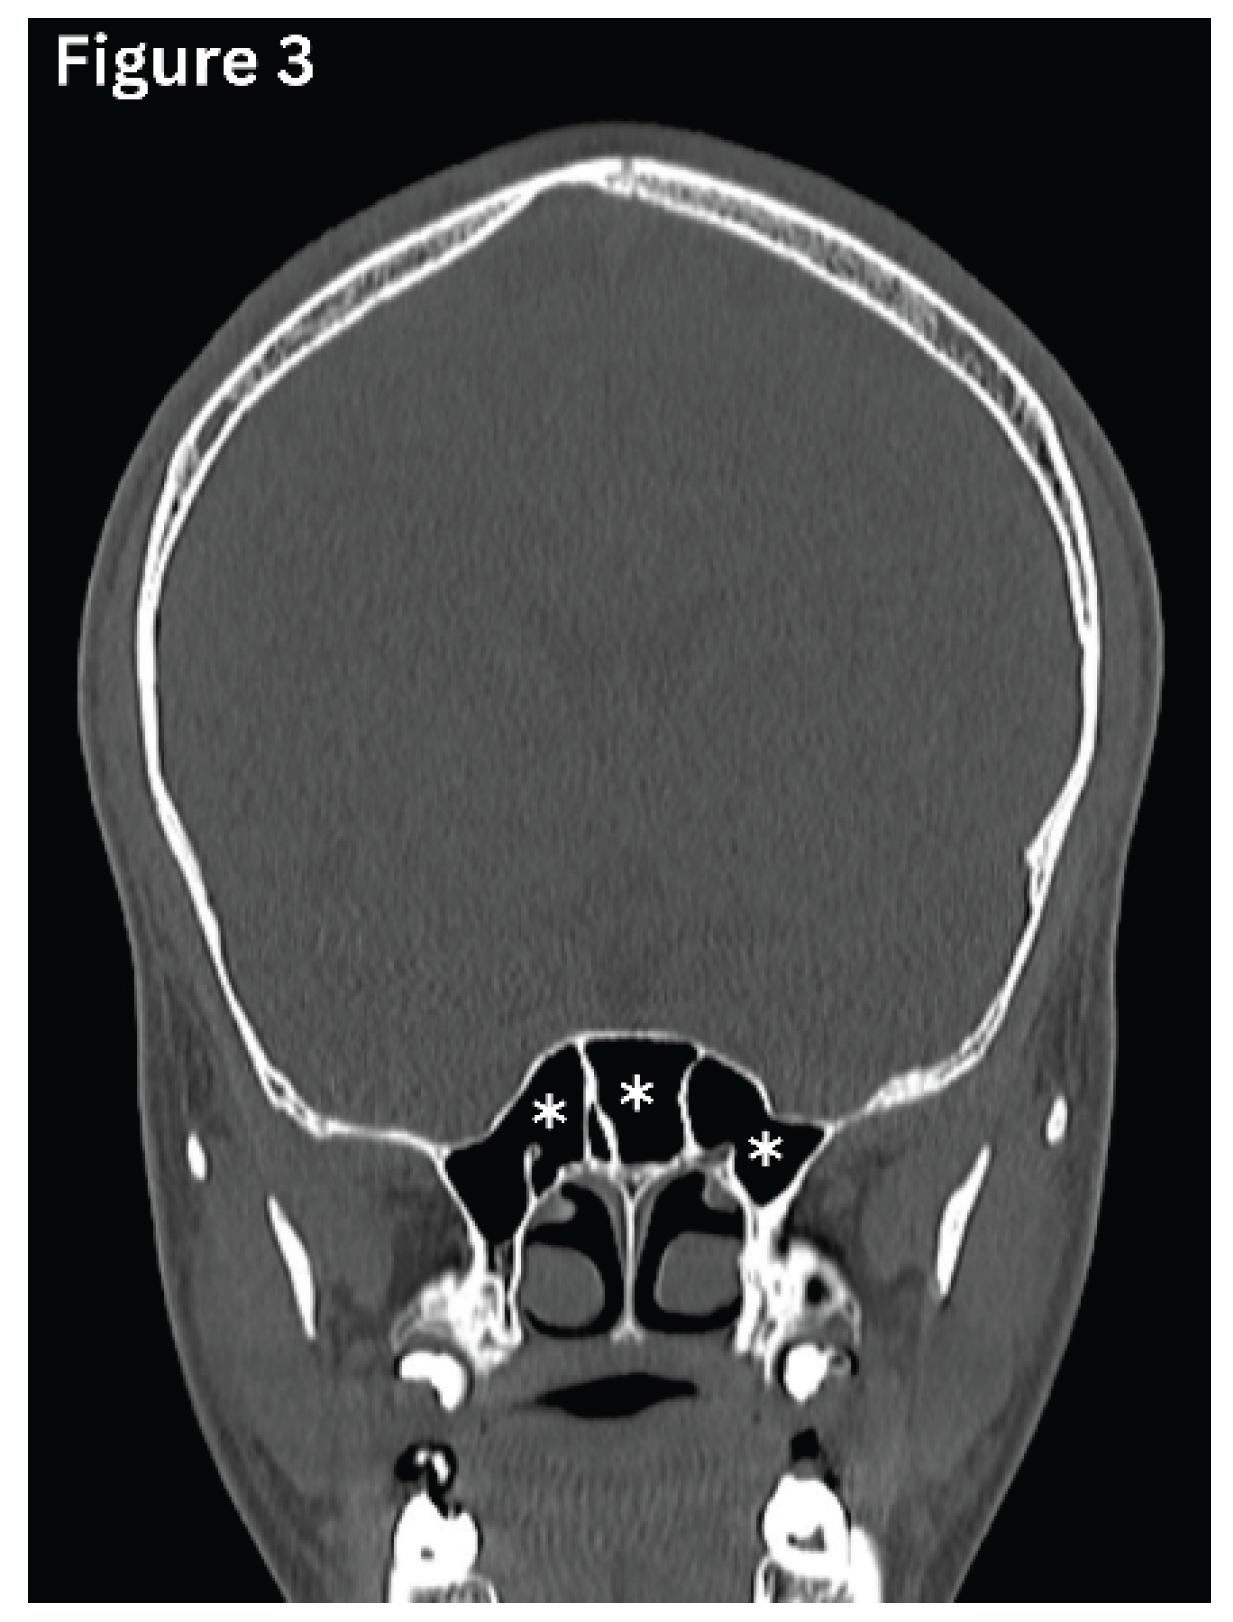

Figure 3. Coronal CT image shows multiple septations in the sphenoid sinus, creating multiple compartments. (asterisks).